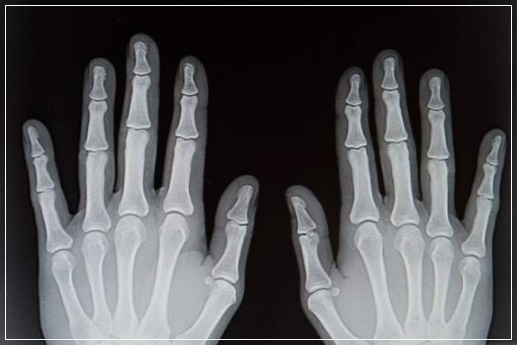

손가락 가운데 마디의 통증과 오랜 시간의 강직을 동반하는 류마티스 관절염의 주된 원인은 `면연력 이상`입니다. 면역력의 문제로 발생하는 류마티스 관절염은 손가락 관절을 시작으로 점점 염증이 퍼지는 질병입니다. 손가락 가운데 마디가 아프고 강직되는 증상이 1시간 이상 계속된다면 퇴행성 관절염이 아닌 류마티스 관절염을 의심해봐야 한다. 류마티스 관절염에 걸릴 경우 여러 손가락이 동시에 붓고 열감이 생깁니다. 주로 손가락 가운데 마디를 시작으로 좌우대칭적인 통증이 일어납니다.

류마티스 관절염은 관절을 정상적으로 매끄럽게 하는 세포(활액 조직)에 영향을 주는 것입니다. 이것은 즉 다발성 관절, 보통 몸의 양쪽 편 모두에 영향을 주게 됩니다. 관절을 싸고 있는 막(활액낭)에 염증이 일어나고 부종이 발생하며 연골과 뼈는 부식됩니다. 부종이 발생한 조직은 주위 뼈를 연결시키는 결합조직인 인대를 신장시킬 수 있고 결과적으로 변형과 장애를 일으킬 수 있습니다.